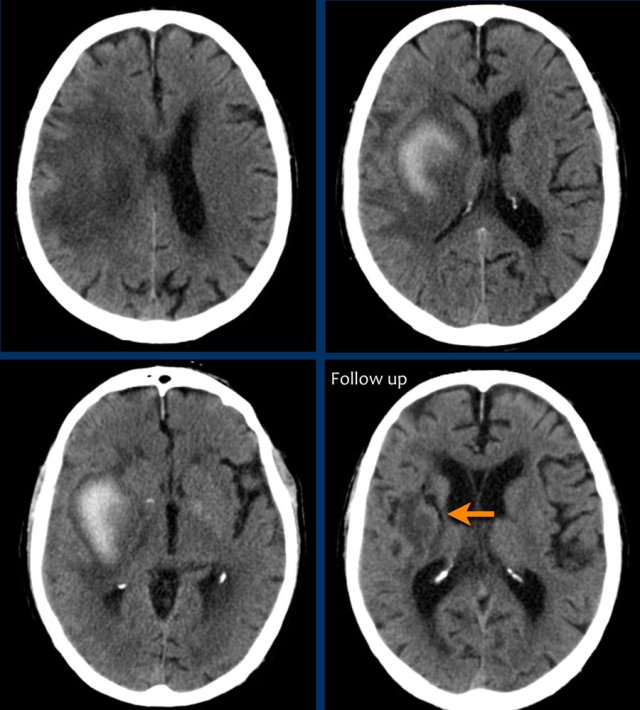

Basal ganglia

Hemorrhage in the basal ganglia is typically seen in hypertension.

Hypertensive hemorrhage typically occurs in elderly patients and is usually in a central location.

This differentiates hypertensive bleeding from hemorrhage in patients with cerebral amyloid angiopathy (CAA) which are more peripheral in location, although overlap can occur.

The images show a typical hypertensive hemorrhage in the putamen, which is the largest and most lateral part of the basal ganglia.

Continue with the follow up images...

On a follow up scan only parenchymal loss is seen in the putamen where the hemorrhage was located (arrow).

The first three images show a large hematoma in the basal ganglia on the right with massive edema.

The follow up image one year later shows  linear cavitation due to tissue loss (arrow) and hypodensity of the basal ganglia as a result of  gliosis.